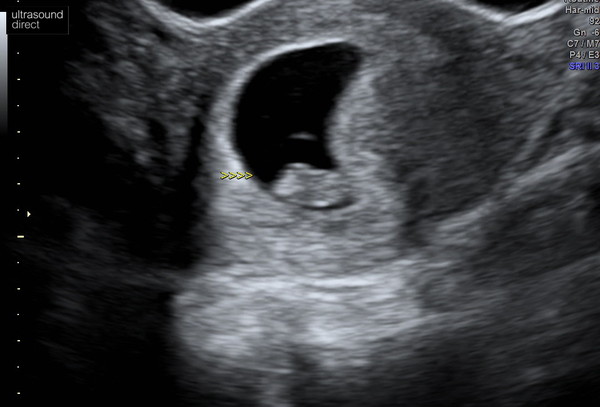

sel2223 · 27/01/2020 19:36

Struggled to get a good pic but it was amazing watching this little blob on the screen and hearing the heartbeat!

This was an abdominal scan at 8+2